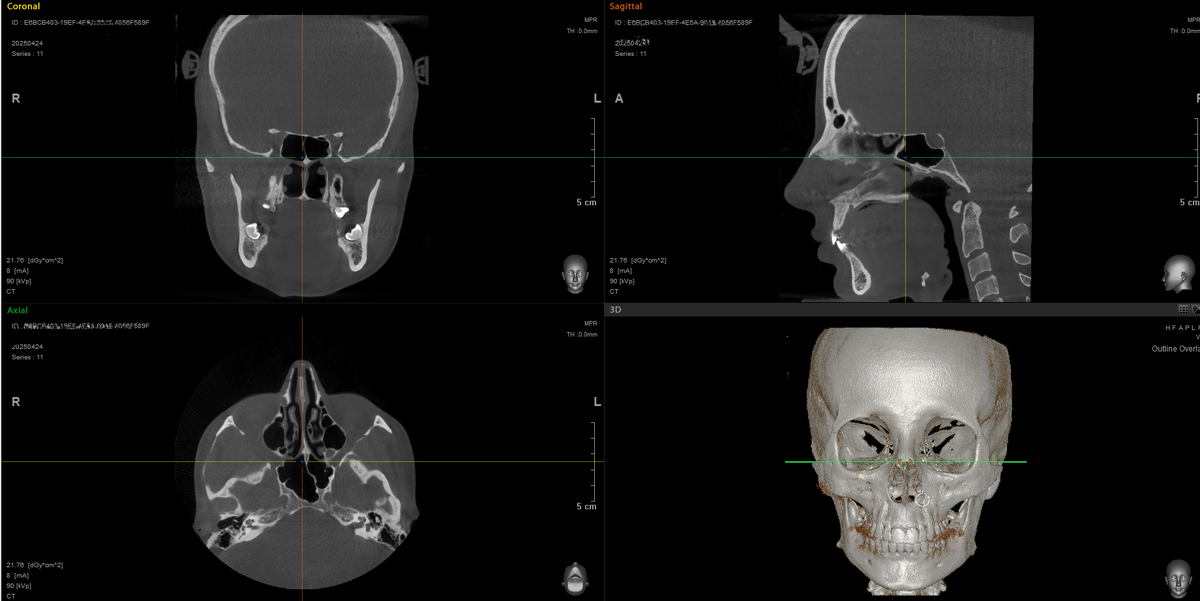

Что такое 3D-снимок?

3-D снимок по-другому называют конусно-лучевой компьютерной томографией (КЛКТ, КТ). Это метод визуализации, при котором черепно-лицевая область сканируется послойно, создавая объемное изображение костных структур.

1. Высокая детализация зубов, корней, костной ткани, суставов, носовых пазух;

2. Возможность точной оценки положения непрорезавшихся зубов;

3. Анализ плотности костной ткани, что критично при перемещении зубов;

4. Оценка симметрии и особенностей челюстно-лицевого скелета.

3D-снимок позволяет врачу не только оценить клиническую картину, но и построить виртуальную модель челюсти, с которой в дальнейшем будет работать ортодонтическое программное обеспечение для планирования перемещений зубов.